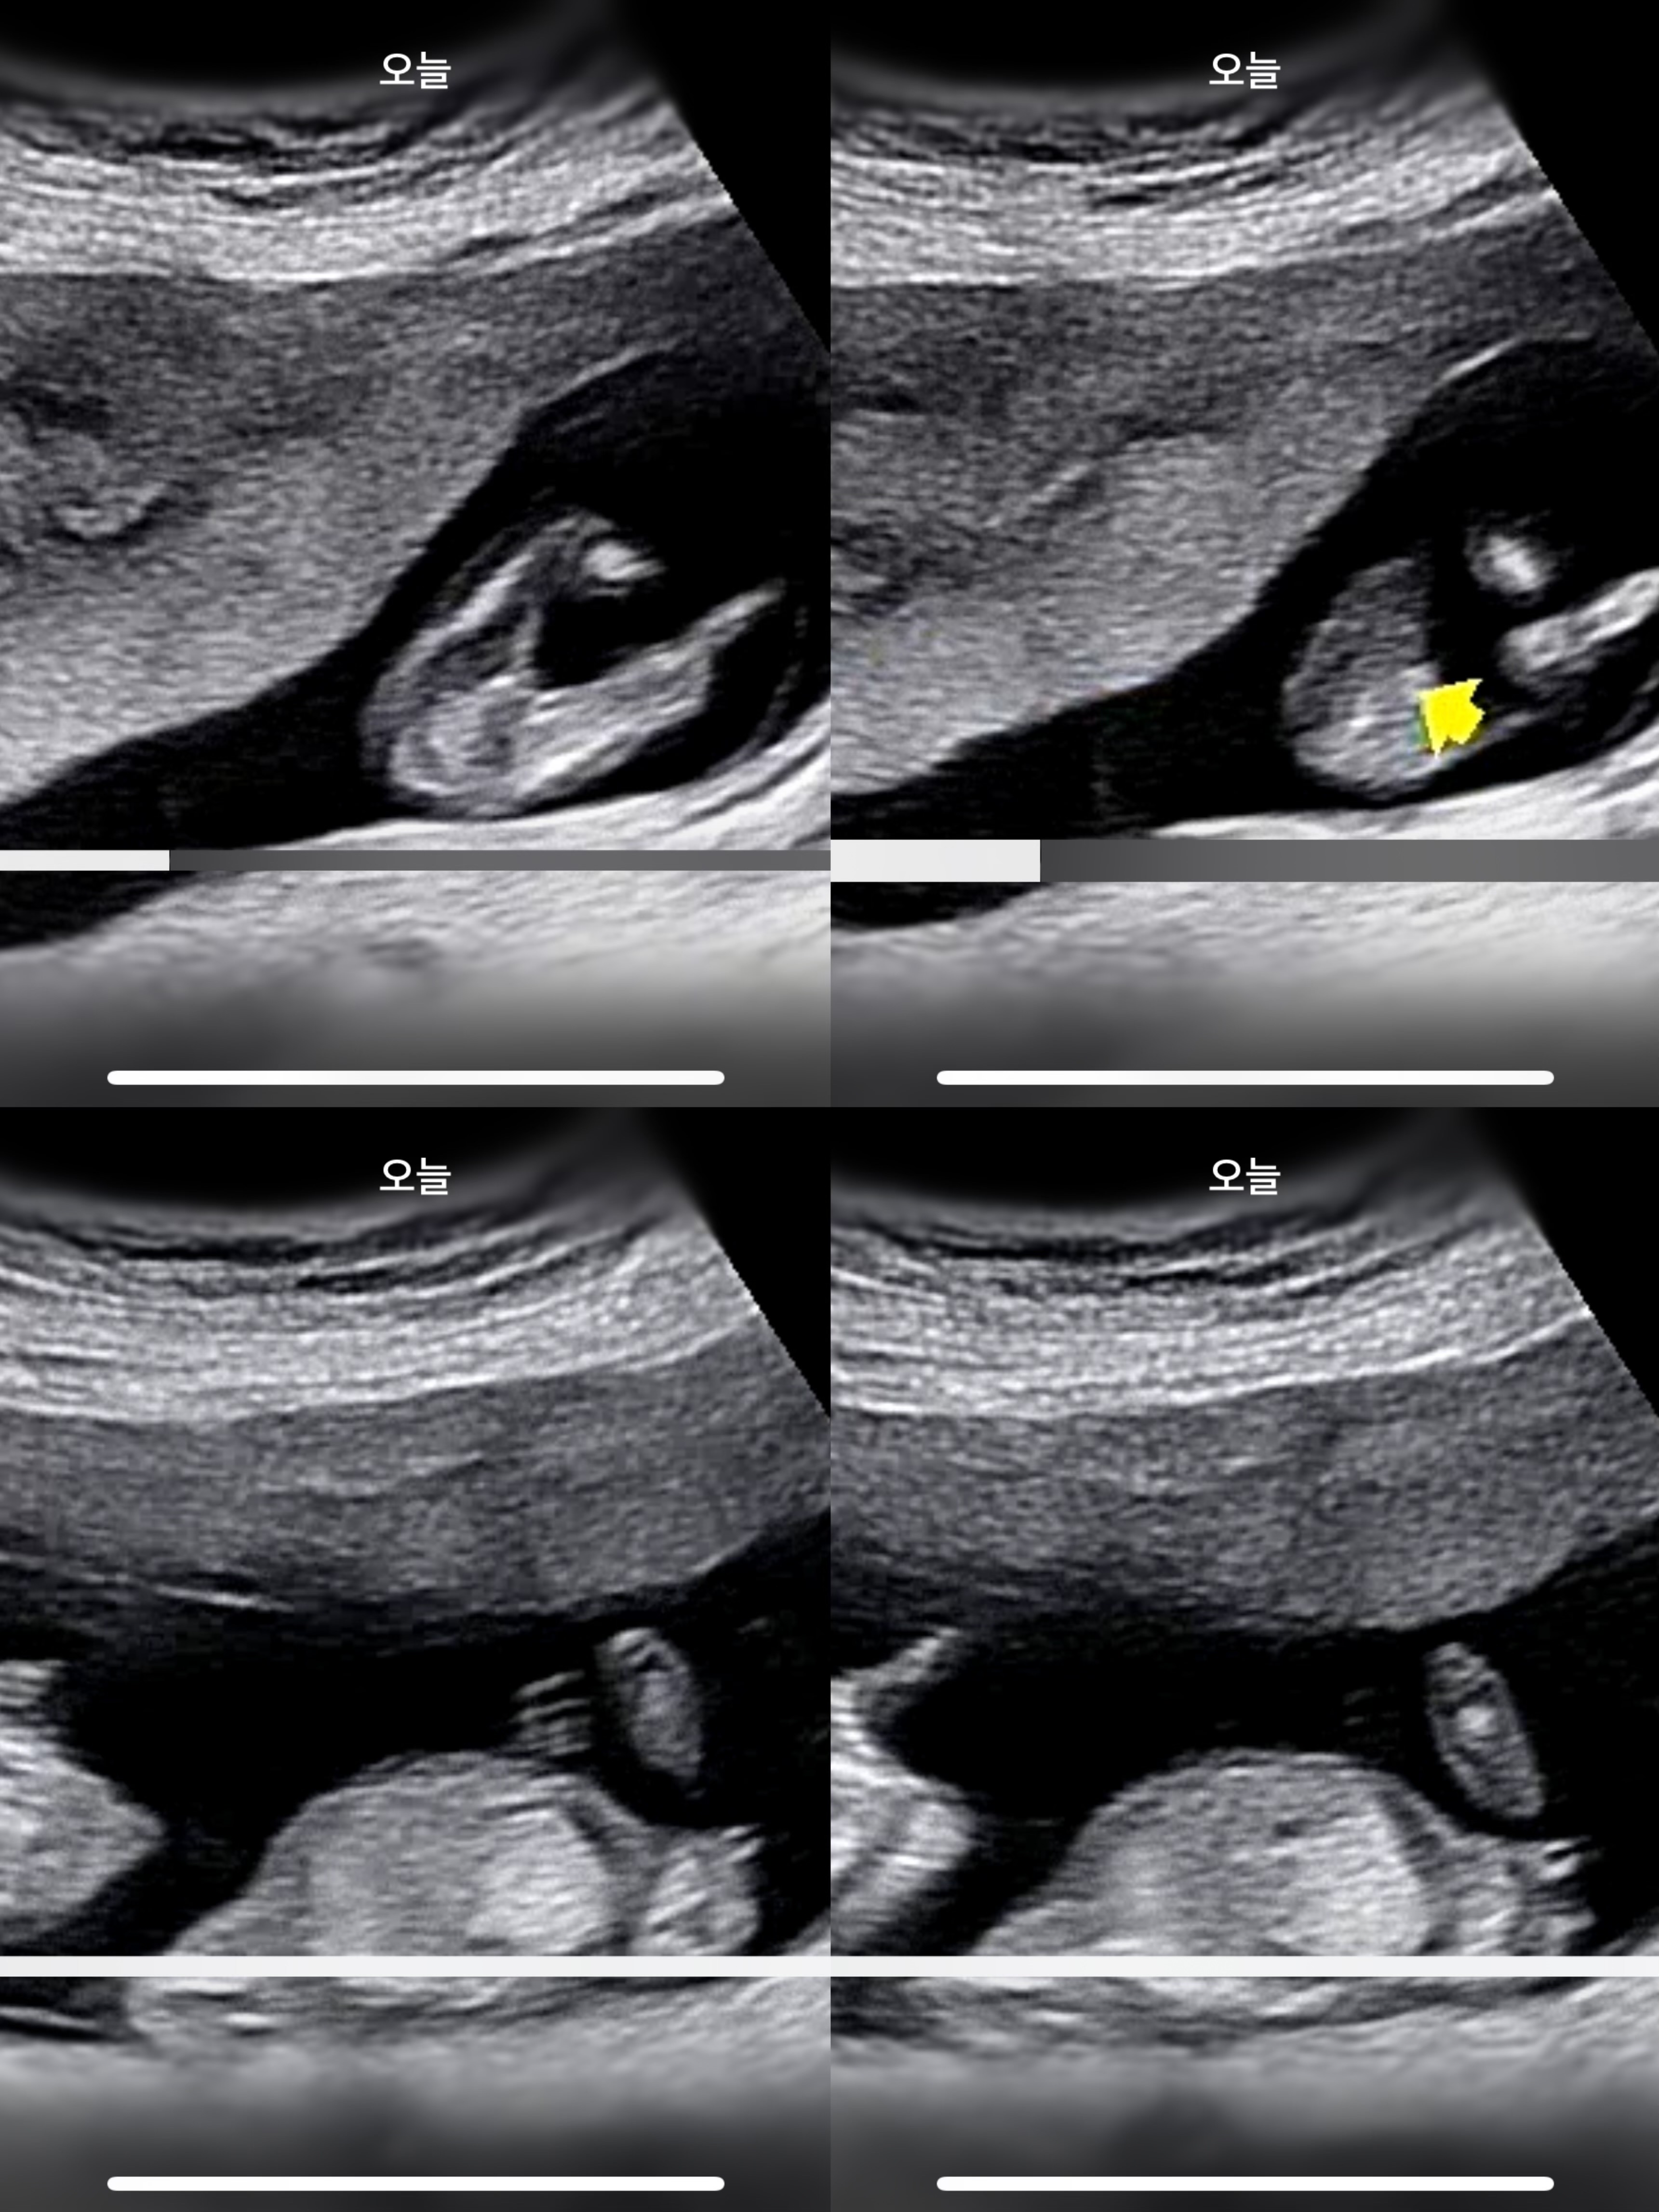

셋째에요🥹 12주 4일차

셋째라 더 귱금해요 선생님께서 꼭 집어서 딸같은데 아직 확실하다고 할순 없는 주수다고 했어요. 딸은 본적 없어서..